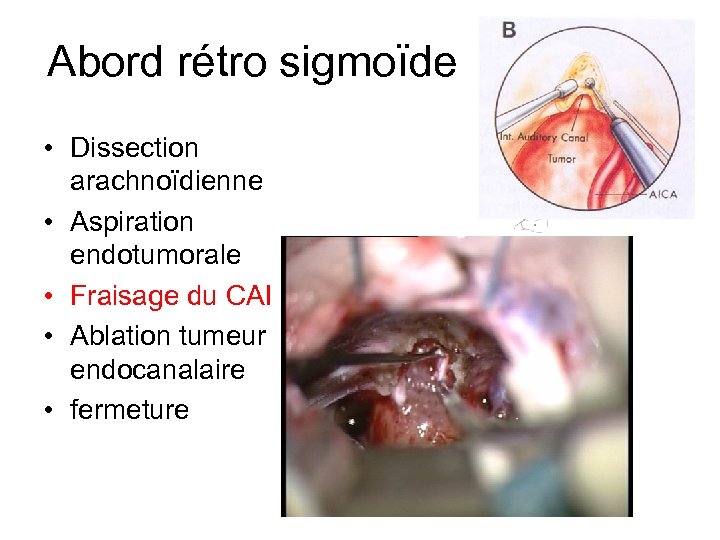

Abord rétro sigmoïde • Dissection arachnoïdienne • Aspiration endotumorale • Fraisage du CAI • Ablation tumeur endocanalaire • fermeture

Abord rétro sigmoïde • Dissection arachnoïdienne • Aspiration endotumorale • Fraisage du CAI • Ablation tumeur endocanalaire • fermeture

Abord rétro sigmoïde • Dissection arachnoïdienne • Aspiration endotumorale • Fraisage du CAI • Ablation tumeur endocanalaire • fermeture

Abord rétro sigmoïde • Dissection arachnoïdienne • Aspiration endotumorale • Fraisage du CAI • Ablation tumeur endocanalaire • fermeture

Abord rétro sigmoïde • Dissection arachnoïdienne • Aspiration endotumorale • Fraisage du CAI • Ablation tumeur endocanalaire • Stimulateur • Fermeture +++ (graisse)

Abord rétro sigmoïde • Dissection arachnoïdienne • Aspiration endotumorale • Fraisage du CAI • Ablation tumeur endocanalaire • Stimulateur • Fermeture +++ (graisse)